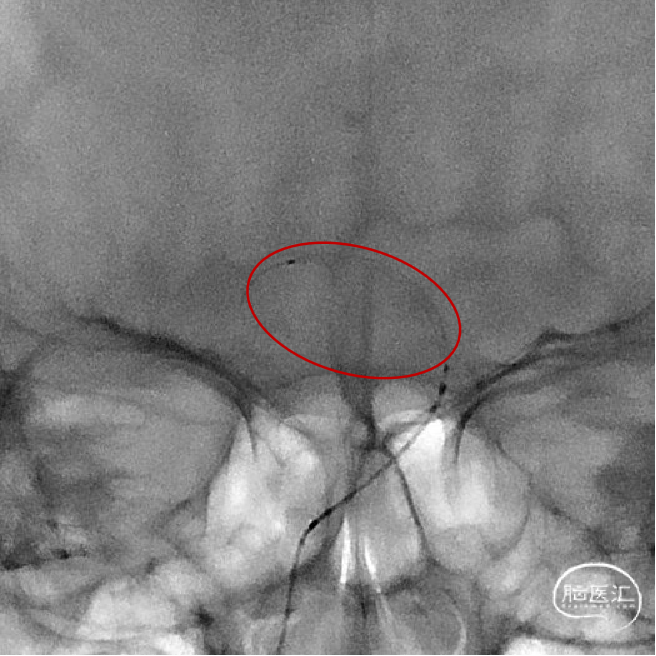

支架释放后未完全打开状态。

体外调节使支架完全打开。

支架充分打开后造影显示血栓位于支架中近端。